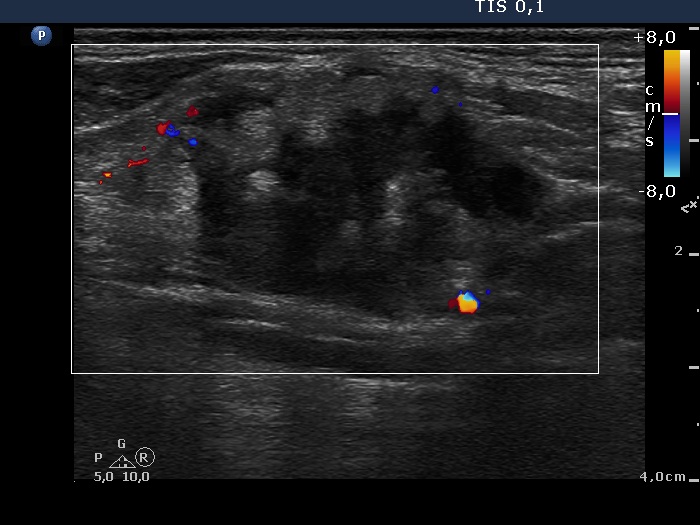

Ultrasonography: The thyroid was intact. There were multiple nodes in both supraclavicular regions. The nodes presented an absolutely irregular shape and border. They contained numerous hyperechogenic circumscribed areas.